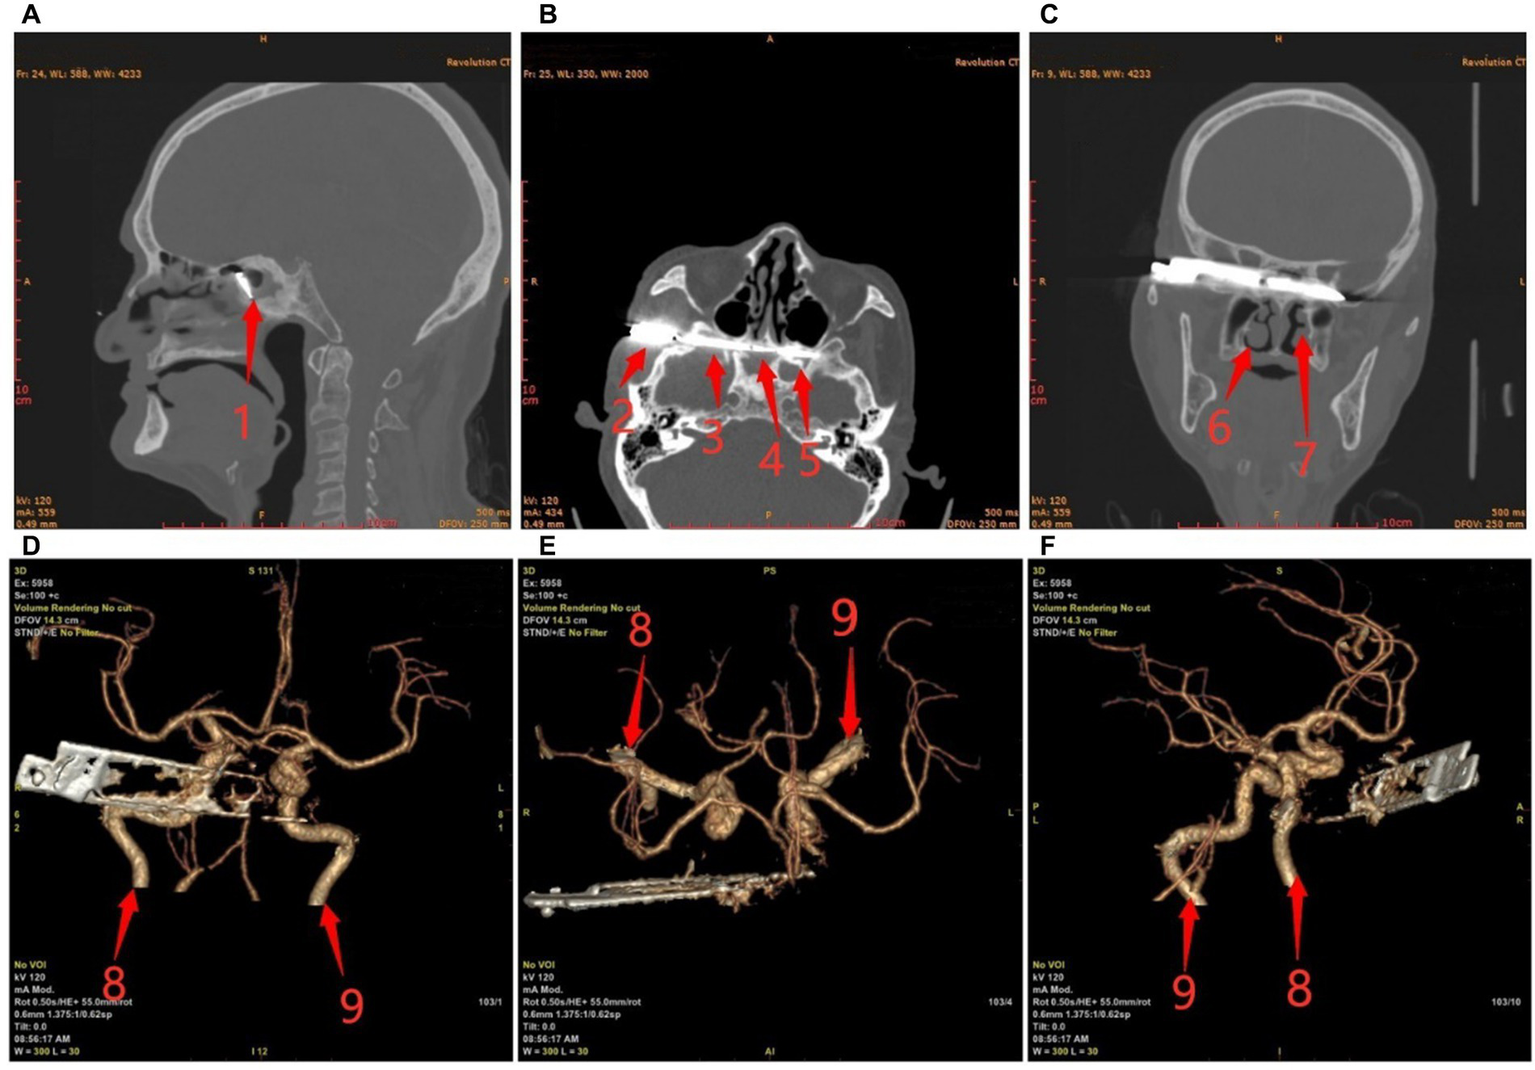

Preoperative ECG and 24 h dynamic electrocardiogram showed sinus bradycardia with 35–50 BPM and multi-lead ST-T alterations. A chest CT revealed bilateral pleural effusion and calcification in the left lung. There were metal foreign bodies in the right temporal and orbital regions, discontinuous bone in the right temporal bone, orbital wall, and sphenoid sinus, and involvement of the right optic nerve, according to the results of paranasal sinus CT, cranial neck CTA, and skull reconstruction (Figure 1).

Figure 1

Preoperative craniocerebral CT and reconstruction. (A) Sagittal; (B) Transverse; (C) Coronal; (D–F) The positional relationship between blood vessels and knives. Red arrows: 1, sphenoid sinus; 2, temporal fossae; 3, the base of the middle cranial fossa; 4, sphenoid sinuses (right); 5, sphenoid sinus (left); 6, right nasal cavity; 7, left nasal cavity; 8, right internal carotid artery; and 9, left internal carotid artery.